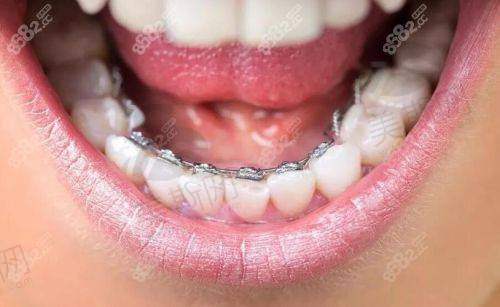

数字化舌侧隐形矫治是其核心技术优势,通过自主研发的eBrace个性化托槽系统,实现矫正过程“完全隐形”,托槽粘接位置误差控制在0.1mm内,矫正效率提升30%,尤其适合对美观要求极高的职场人士与公众人物。无托槽隐形矫治方面,他累计完成隐适美、时代天使实例超8000例,擅长通过3D动态咬合模拟技术优化方案,误差率低于0.1mm,患者满意度达98%。

2. 数字化舌侧矫治精细控制

作为国内首批开展舌侧矫正的骨干医生,他研发的“个性化舌侧托槽系统”通过3D打印技术定制托槽角度,使矫治力作用点更接近牙阻抗中 心,在压前牙内收、上颌扩弓等方面成效提升40%。临床实例显示,骨性凸嘴患者采用舌侧矫正 + 颌位调整技术,18 - 24个月可实现侧貌从凸面型到直面型的转变,复发率低于2%。